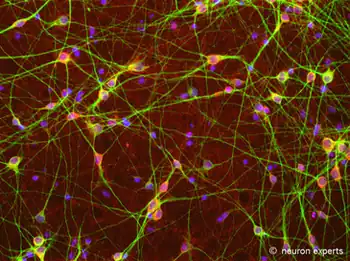

γ-Aminobutyric acid (gamma-aminobutyric acid) /ˈɡæmə əˈmiːnoʊbjuːˈtɪrɪk ˈæsɪd/, or GABA /ˈɡæbə/, is the chief inhibitory neurotransmitter in the developmentally mature mammalian central nervous system. Its principal role is reducing neuronal excitability throughout the nervous system.

Neurons that produce GABA as their output are called GABAergic neurons, and have chiefly inhibitory action at receptors in the adult vertebrate. Medium spiny cells are a typical example of inhibitory central nervous system GABAergic cells. In contrast, GABA exhibits both excitatory and inhibitory actions in insects, mediating muscle activation at synapses between nerves and muscle cells, and also the stimulation of certain glands.[6] In mammals, some GABAergic neurons, such as chandelier cells, are also able to excite their glutamatergic counterparts.[7] In addition to fast-acting phasic inhibition, small amounts of extracellular GABA can induce slow timescale tonic inhibition on neurons.[8]